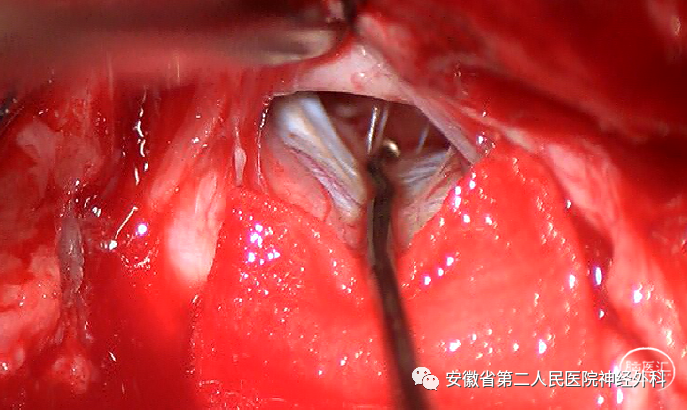

神经电生理监测下颈前外侧椎间孔入路

切除肿瘤主体

后正中半椎板入路切除神经根处肿瘤,探查松解神经根出椎间孔处